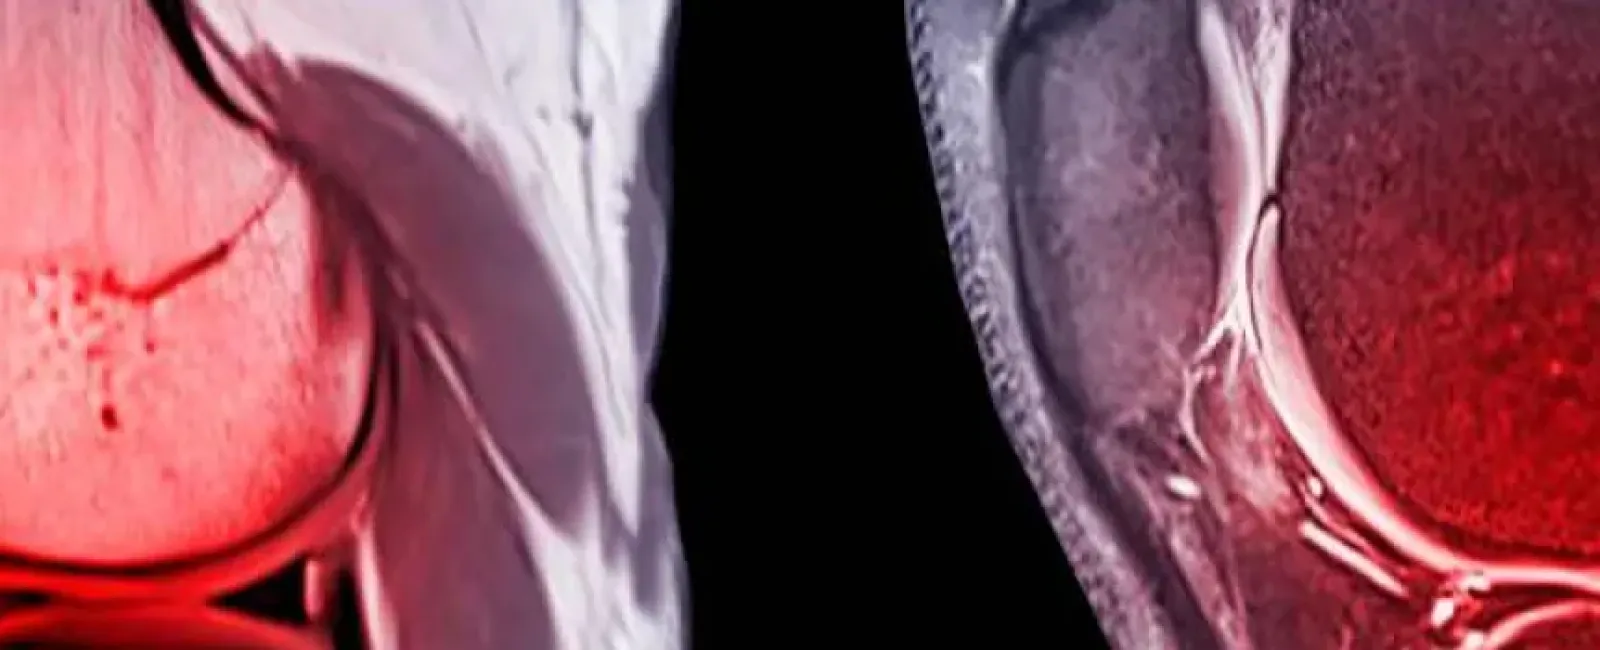

Imaging tests, such as X-rays and MRIs, to confirm the diagnosis and evaluate the extent of the injury.